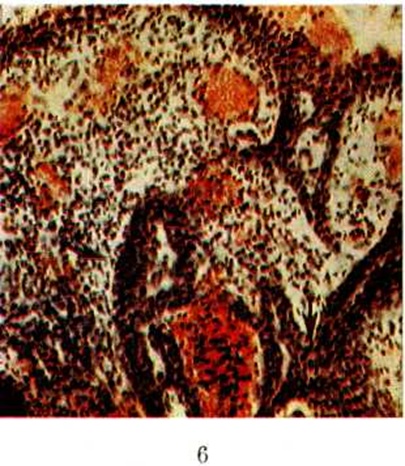

СирингоаденомаСирингоаденома (греческий syrinx, syringos дудочка, трубка + аденома синонимы: сосочковая сирингоаденома, сирингоцистаденома, папилломатозный сирингоцистаденоматозный невус, сосочковая цистаденома, сирингоцистома, сосочковая аденома потовой железы, бородавчатая фистуловегетирующая гидраденома) — доброкачественная опухоль кожи, исходящая из протоков потовых желёз. Сирингоаденома встречается редко, обычно в молодом и детском возрасте, хотя может наблюдаться у лиц пожилого и старческого возраста. Локализуется преимущественно на волосистой части головы и нередко в зоне расположения апокринных потовых желёз (подмышечные ямки, область молочных желёз, паховые области), значительно реже на других участках тела. Возможно сочетание Сирингоаденома с пороками развития и другими эпителиальными опухолями кожи (смотри полный свод знаний) — базалиомой (смотри полный свод знаний), себорейной папилломой, эккринной поромой и другие Единого взгляда на гистогенез Сирингоаденома нет. Большинство исследователей считает, что Сирингоаденома развиваются на основе порока развития потовых желёз (смотри полный свод знаний) или их первичного эпителиального зачатка, некоторые, напротив, полагают, что Сирингоаденома может развиваться и из полностью сформированных апокринных и эккринных потовых желёз. Макроскопически Сирингоаденома представляет собой единичное образование типа узелка или бляшки диаметром 0,5—2 сантиметров сероватого или серовато-жёлтого цвета, плотной консистенции, нередко возвышающееся над кожей, с неровной мелкобугристой или зернистой поверхностью, иногда изъязвлённое. Микроскопически различают папиллярную и тубулярную Сирингоаденома Папиллярная Сирингоаденома образована кистами и железистоподобными тубулярными структурами, располагающимися под эпидермисом (цветной рисунок). Кисты и трубки выстланы двухрядным эпителием: внутренний слой составляют кубические или цилиндрические клетки, наружный слой — уплощённые клетки. |

Характерной особенностью Сирингоаденома этого типа является наличие в кистах сосочков. При изъязвлении опухоли сосочки могут выступать над поверхностью кожи. Иногда кисты и сосочки выстланы многослойным плоским эпителием. В клетках Сирингоаденома обнаруживают гликоген и слизь. Слизистое содержимое, богатое гликогеном, определяется и в полостях кист. Характерной особенностью папиллярной Сирингоаденома является массивная лимфоплазмоцитарная инфильтрация стромы сосочковых выростов. Тубулярная Сирингоаденома состоит из переплетающихся и анастомозирующих друг с другом трубок, выстланных двухрядным эпителием. Некоторые трубки кистозно расширены, но в них нет сосочковых выростов. Их содержимое богато гликогеном и муцином. Иногда отмечается метаплазия эпителия в многослойный плоский.